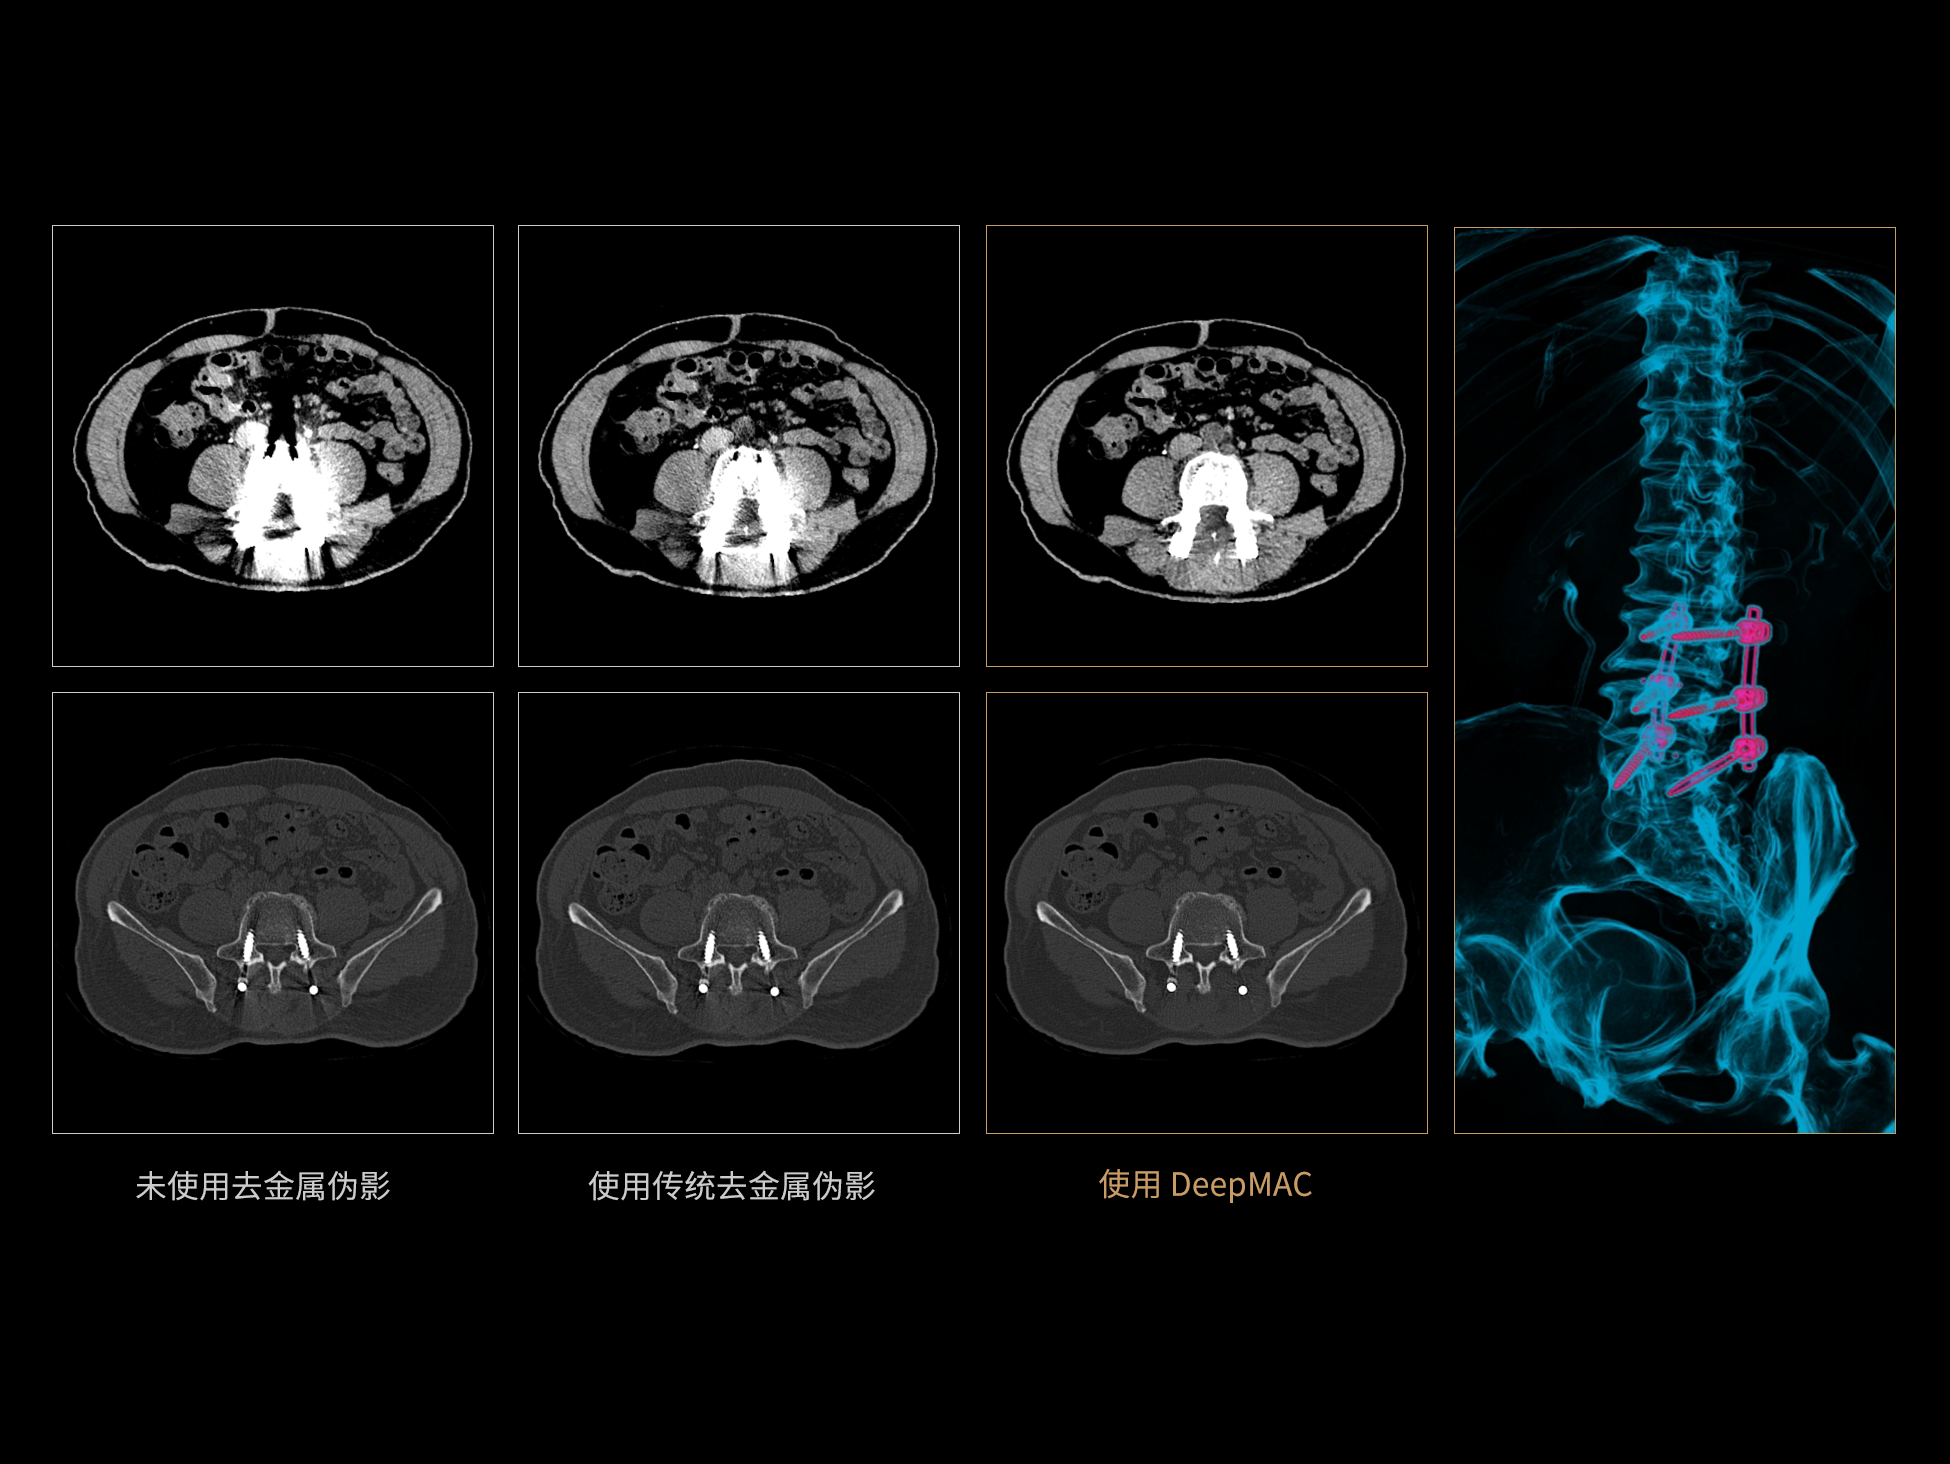

DeepMAC**:AI去金属伪影算法

DeepMAC**智能金属伪影校正技术通过深度学习算法有效解决了临床中各类不规则金属植入物导致的CT成像伪影问题,具备良好的通用性和稳定性。该技术依托大规模、高多样性的训练数据集,覆盖了包括髋关节置换体、脊柱内固定器(胸腰椎/颈椎)、四肢骨科植入物、牙科修复体以及血管介入弹簧圈等在内的金属植入物类型。通过深度神经网络的特征提取与解剖结构重建优化,DeepMAC** 在有效抑制金属伪影的同时,最大程度地保留了真实的解剖细节,显著提升了影像诊断的准确性。

±10HU

CT值准确性※ ※

≥50% 重建速度提升

相较传统算法,重建速度提高50%以上※ ※

※ ※数据在测试条件下,与传统MAC去金属伪影算法对比获得